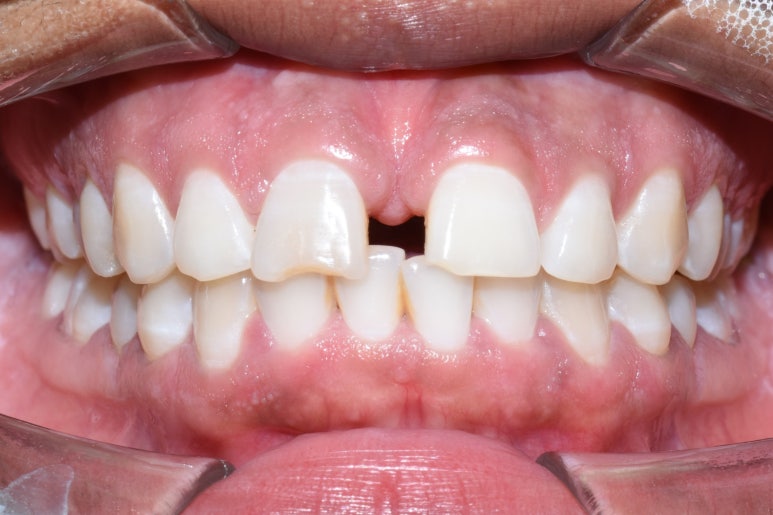

치료전 사진

위 사진과 같이 화살표 위아래로 전후 모습이 변화하였습니다.

교정은 환자분이 토요일만 오실 수 있어서 날짜에 제약이 있었음에도 불구하고

1월에 시작하여 4월초에 끝났으므로 3개월 반 정도 걸렸고

라미네이트는 본 뜬 후 10일 정도 후에 붙였습니다. 치아 삭제는 거의 하지 않았으며 사진상 원래 치아가 깨진 부분만 다듬고 라미네이트를 하였습니다.

치료 전 후

치료 전 후 얼마나 고르면서 치아 겉면 색도 하얗게 되었는지 비교가 되시죠?